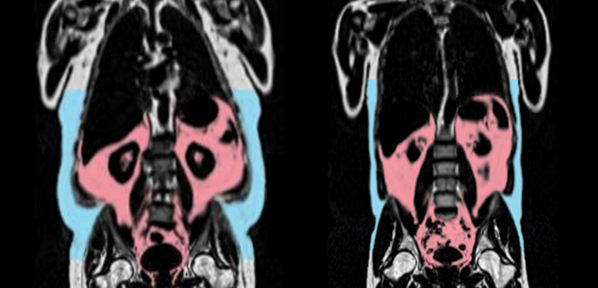

Two MRI scans, showing the person on left with more visceral fat (in red) and subcutaneous fat (in blue). Photo Credit: AMRA Medical

The associations of visceral fat and abdominal adipose tissue with accelerated cardiovascular aging—ie, a greater age-delta, or difference between chronological and predicted age—were more robust in men than in women. Moreover, increased gynoid fat, the type that accumulates around the hips and thighs, was tied to protective effects—a lower age-delta—in women but not men.